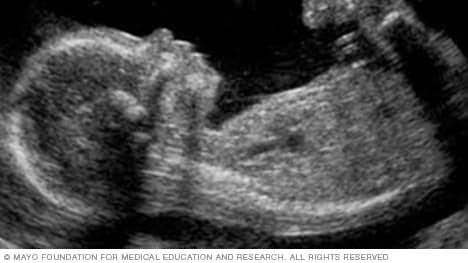

Obstetrics: Fetal blood flow in IUGR and cord around the neck.

Antenatal sonography for the confirmation and progress of pregnancy, foetal viability and maturity, foetal age and weight, expected date of delivery, placental localization and muuaturity, cases of abortion and ectopic pregnancy, and 18-22 weeks detailed fetal anomaly ultrasound.